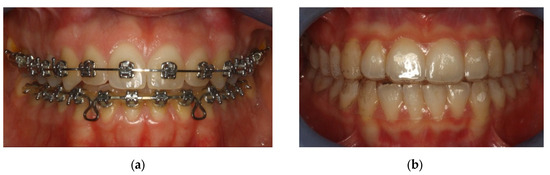

Thanks to a camera integrated in the microscope, it is possible to view the bacterial plaque samples on the computer and take screenshots (Figure 4 and Figure 5).

In the preparation, it is possible to visualize which bacteria are present, as well as the number and structures of epithelial cells and polymorphonuclear cells found there. It seems simple to make a distinction between

Non-pathogenic bacterial flora: immobile, similar to the aerial view of the mainland (Figure 4a);

Pathogenic bacterial flora: in which “Streams” or “basins” with mobile bacteria are visualized, mostly composed of spirochetes (including Treponema Denticola) and Trichomonas Tenax, which flow in motion as if dragged by the current. The most consistent similarity is that of the aerial visualization of the Norwegian fjords (Figure 4b).

Figure 5. Phase-contrast microscope with dividing line between non-pathogenic bacterial flora (above) and pathogenic bacterial flora (below).